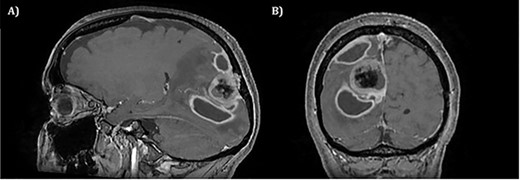

The operation was successful with a post-operative MRI within 48 h demonstrating complete resection of the tumour and resolution of the cystic lesions, but persisting intraparenchymal oedema (Fig. 3). The patient had an uncomplicated two-day stay in a neurosurgery high dependency unit postoperatively before being stepped down to the general neurosurgery ward. She was reviewed by the microbiology team and worked up for the source of infection. Blood cultures, urine cultures, CXR and transthoracic echocardiography were all negative for a source of infection. Intra-operative pus cultures isolated MSSA. The histopathology of the tumour was Meningioma WHO Grade 1 with large areas of necrosis and secondary abscess formation. She was discharged feeling well 5 days later after a satisfactory biochemical and clinical response. She was given a weaning course of steroids and a 6-week course of intravenous ceftriaxone via a PICC line as an outpatient as per microbiology advice. Ophthalmology assessment 3 months after discharge confirmed a left inferior quadrantonopia and preserved visual acuity. Repeat MRI and clinic review 8 weeks later showed no radiological residual tumour or oedema (Fig. 4), and the patient’s limb function recovered completely but had ongoing visual symptoms.

T1 weighted axial MRI post-gadolinium enhancement 8 weeks postdischarge. Right occipital postsurgical appearances are again demonstrated with reduction in the extent of vasogenic oedema. The enhancing rim that was present previously has retracted, with only focal curvilinear enhancement now evident in the right occipital lobe. These appearances are likely postsurgical/treatment related, and there is no convincing residual or recurrent disease.